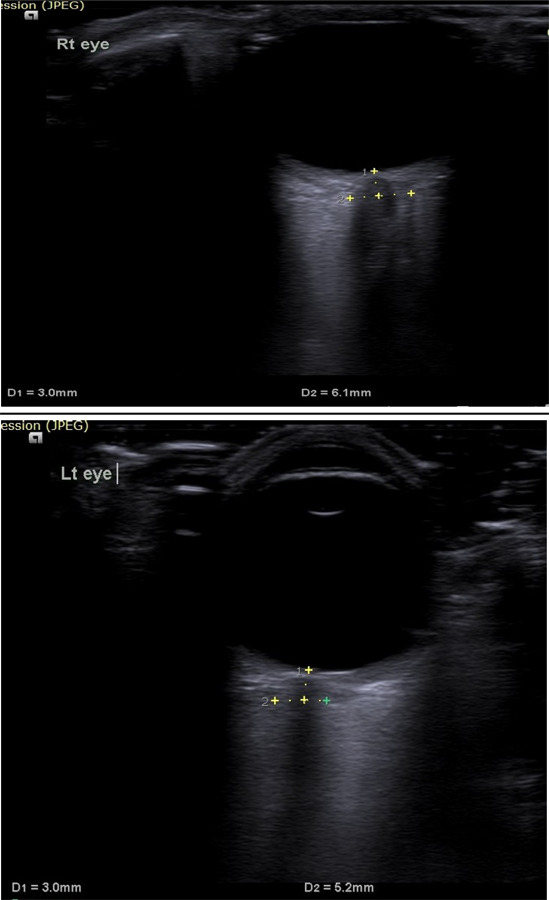

On arrival in the ICU, his Glasgow Coma Scale (GCS) score was 10/15 (E3V2M5). Pupils were bilateral equal in size and reactive to light. He was afebrile and there were no signs of meningeal irritation. Reflexes and jerks were normal. There was no history of recent administration of any sedatives. A colonoscopy was performed about four hours back, during which sedated with midazolam. However, the patient had regained full consciousness before he was transferred to the ward. An examination of other systems revealed no abnormalities. Arterial blood gas (ABG) analysis and serum electrolytes were sent among which Magnesium, Phosphate, and Calcium were normal. The ABG was normal. The report of serum electrolytes revealed hyponatremia, with the sodium (Na+) level of 111mmol/L. The blood glucose level was normal. On further evaluation of the history, it was revealed that the patient had ingested around 7-8 liters of overzealous free water overnight with the PEG solution for bowel preparation for colonoscopy. He had presumed extra water would cleanse the bowel and make the procedure easy and more diagnostic. In the ICU patient developed generalized tonic-clonic seizure which was treated with intravenous midazolam and leverecietam was added as anticonvulsant. Optic Nerve Sheath Diameter was recorded which was 6.1mm in Right Eye and 5.1mm in Left Eye (Figures 1a and b).

Figure 1 A. ONSD Right Eye. B. ONSD Left Eye.